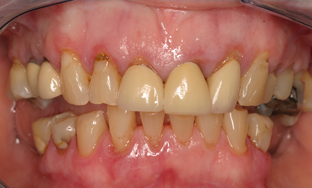

This patient was very unhappy with her smile because the teeth were heavily worn down and fractured and she didn’t have enough back teeth to chew comfortably.

With dental implants at the back of the mouth, we were able to provide her with functional teeth which were solid and fixed. This eliminated any need for removable dentures, with crowns being used at the front of the mouth to stabilise, strengthen and improve the teeth. She is now seen on a regular basis for follow up to ensure that her mouth remains healthy.

She is delighted with the end result.